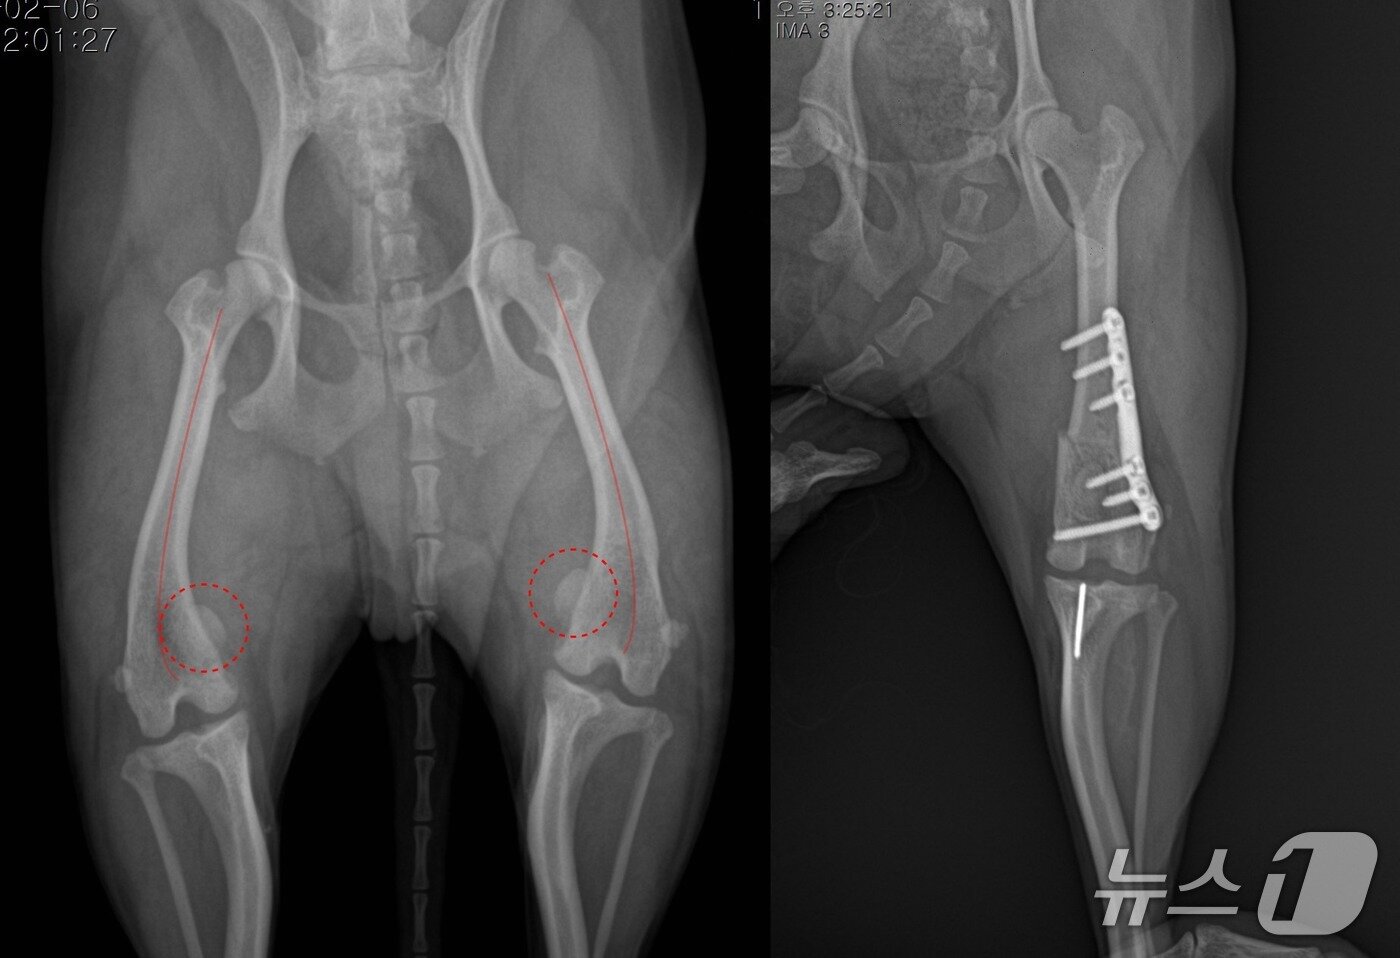

본문 이미지 - 의료용 플레이트를 활용한 슬개골 수술 전(왼쪽)과 후(돌봄동물의료센터 제공) ⓒ 뉴스1

의료용 플레이트를 활용한 슬개골 수술 전(왼쪽)과 후(돌봄동물의료센터 제공) ⓒ 뉴스1